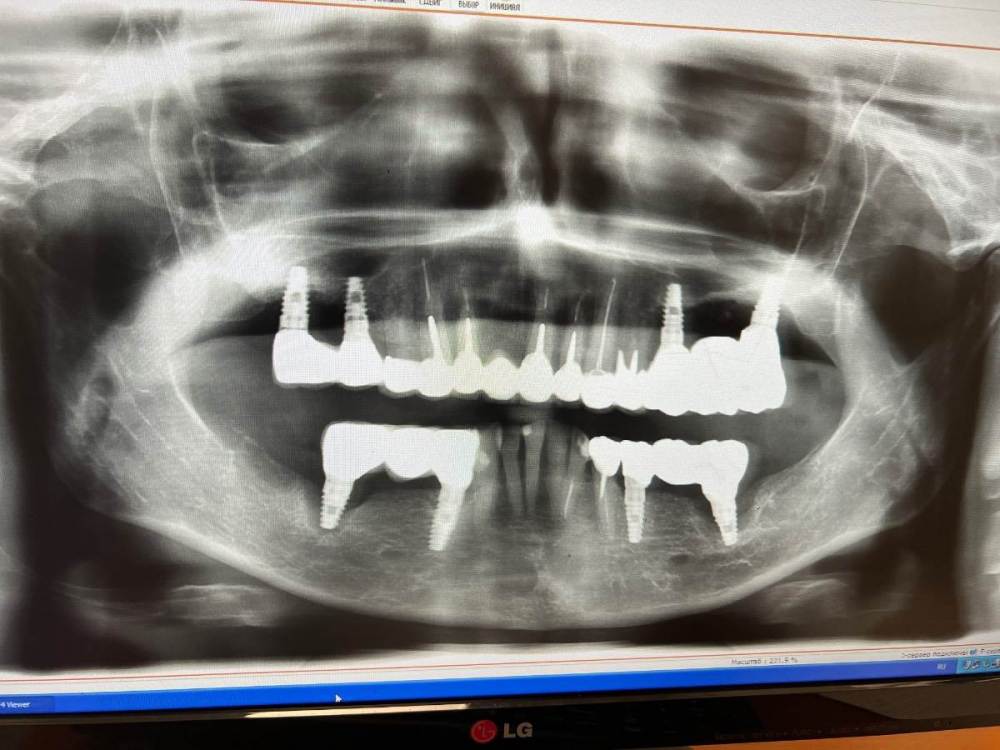

a.sataeff Опубликовано 16 декабря, 2022 Поделиться Опубликовано 16 декабря, 2022 (изменено) Добрый вечер, пишу с разрешения мамы. Не знаем что делать. Шесть лет назад мама делала импланты Биогоризонт, сейчас расшатались нижние, ее врач больше в клинике не работает, уехал из страны, другой врач сказал удалять нижний имплантат и вставлять два импланта и мостик, но сказал что новый импланты так же быстро расшатаются, а съемные протезы мама не хочет. Есть какой-то вариант? Изменено 16 декабря, 2022 пользователем a.sataeff Ссылка на комментарий

Irouil Опубликовано 17 декабря, 2022 Поделиться Опубликовано 17 декабря, 2022 Чтобы что-то говорить ответственно, нужно видеть компьютерную томограмму и ситуацию в полости рта, но ВЕРОЯТНЕЕ ВСЕГО возможно удалить два крайних импланта на нижней челюсти, установить два импланта чуть ближе к уже стоящим (может быть потребуется установить их под углом и со специальным переходником каждый) и сделать новые мостовидные протезы (возможно дополнив работу мягкотканной аугментацией - десневой пластикой). Такой вариант мне кажется оптимальным. Но есть и альтернатива - удаление крайних имплантов на нижней челюсти, через пару месяцев новые снимки и проведение костной пластики в области удалённых имплантов для последующей имплантации в эти же места. 2 1 Ссылка на комментарий

Irouil Опубликовано 17 декабря, 2022 Поделиться Опубликовано 17 декабря, 2022 37 минут назад, a.sataeff сказал: вопрос еще по верхним имплантам, пока постоят еще? Да, пожалуй что так - значительно улучшить состояние тканей вокруг них практически невозможно, поэтому я бы не трогал их пока не забеспокоят, а потом бы удалил, провел заново аугментацию (если это будет актуально на тот момент) и установил бы новые 1 Ссылка на комментарий